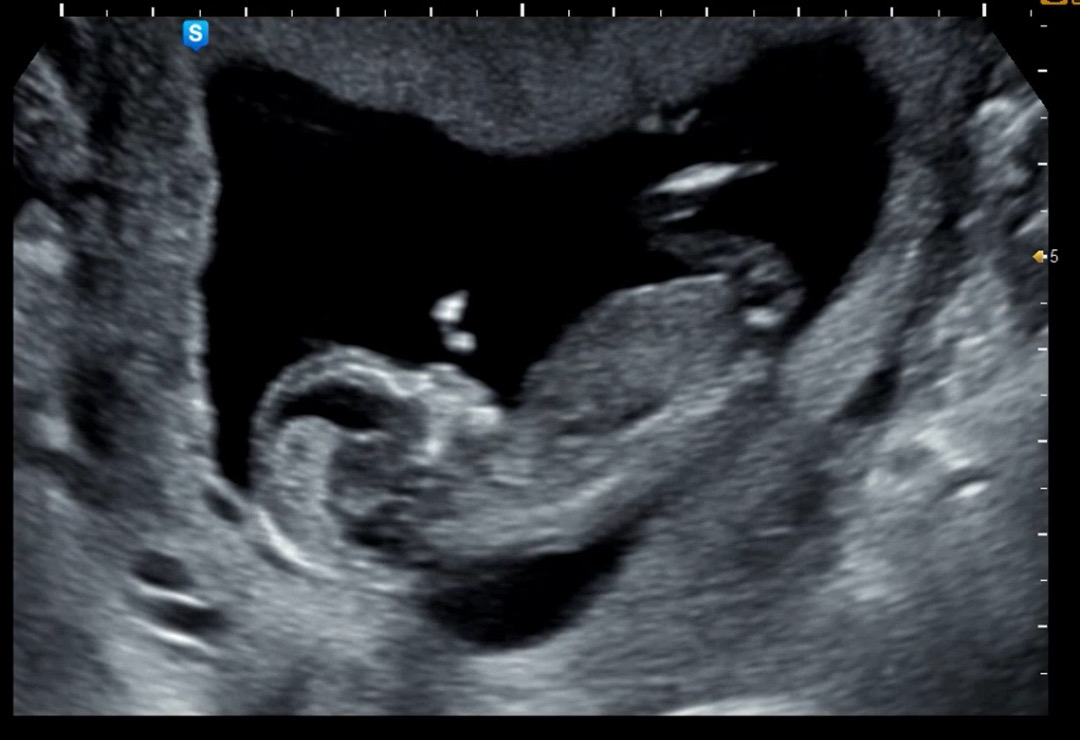

12주3일기준

딸인지 아들인지 너무 궁금해죽겠어요

제 눈에는 딸 같아용~